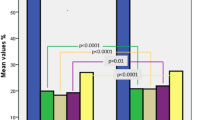

Using 2D-STE, the conventional echocardiography parameters and GLS parameters of the three groups were compared. A comparison of the LVEF, stroke volume (SV), cardiac output (CO), LVEDD, LVESD, LV mass, WMSI, left atrium (LA), the E/A ratio, and the E/e’ ratio of the three groups revealed no statistically significant difference. The LV-GLS values of the control, non-severe, and severe groups were − 19.4 ± 1.6%, − 16.7 ± 1.3%, and − 14.5 ± 1.8%, respectively, and there was a statistically significant difference among the three groups (p < 0.001). It was observed that the sPAP value, which is one of the conventional parameters, was statistically significantly higher in the severe group compared to the other groups. In addition, the RV diameter was found to be higher in the severe group compared to the other groups, The RV-LS values of the control, non-severe, and severe groups were − 27.3 ± 3.1%, − 20.5 ± 3.2%, and − 17.2 ± 2.3%, respectively, indicating a statistically significant difference among the groups (p < 0.001) (Fig. 1).